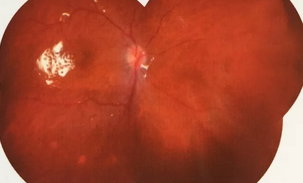

独眼,视网膜全脱离已成窄漏斗状、陈旧性葡萄膜炎、瞳孔后黏连无法散大,且并发白内障使得视网膜周边部细节情况无法看清,左眼已无光感,角膜白斑,瞳孔闭锁,还填充着硅油。右眼既往葡萄膜炎病因不清,一年中发病3、4 次都是用激素医治。左眼多年前是“天那水”溅入后又发生玻璃体出血手术后……令人担心的是这次我们克服重重困难救治全部脱离的视网膜 后,可能会面对长期慢性葡萄膜炎、长期药物医治的继发性高眼压,以及葡萄膜炎的再次复发等,稍有不慎就是不逆性致盲了。